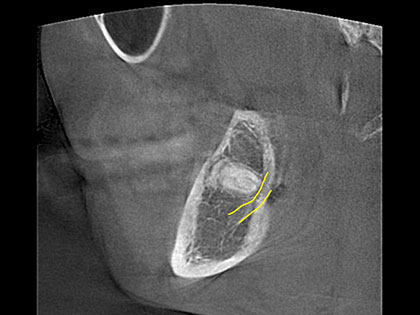

• 初診時のレントゲン写真がこちら

• 親知らずの抜歯術前1

• 親知らずの抜歯術前2

• 平面のレントゲンで下歯槽神経(黄色い線)に近い事はわかりますが、より詳しく確認したいのでCTを撮影する事が必要、大切です。

• CTでもかなり近くシビアなケースです。歯肉を切開し、粘膜を開き親知らず周辺の骨を削り、頭の部分と根っこの部分に分け抜歯しました。